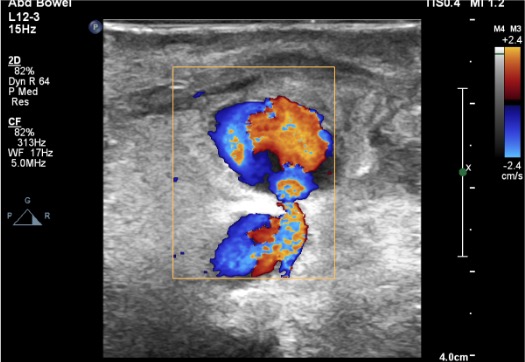

- “Yin-yang” sign — swirling bidirectional color flow within the sac on color Doppler

- Color Doppler “yin-yang” sign: swirling bidirectional color flow within the PSA sac — pathognomonic

- Spectral Doppler at neck: characteristic to-and-fro waveform — systolic inflow into sac, diastolic outflow back to artery